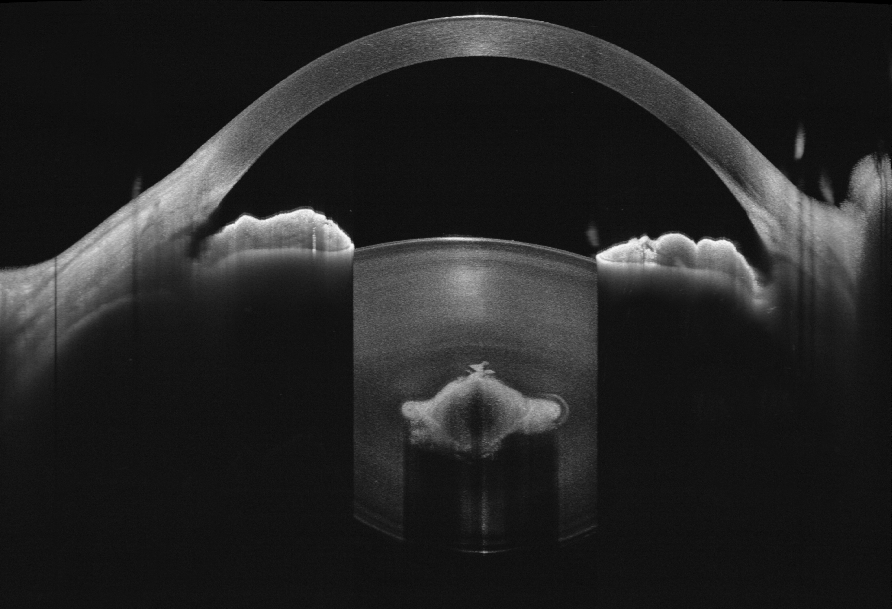

Anterior segment imaging with VG-200C

Imaging depth visualization of VG-200C